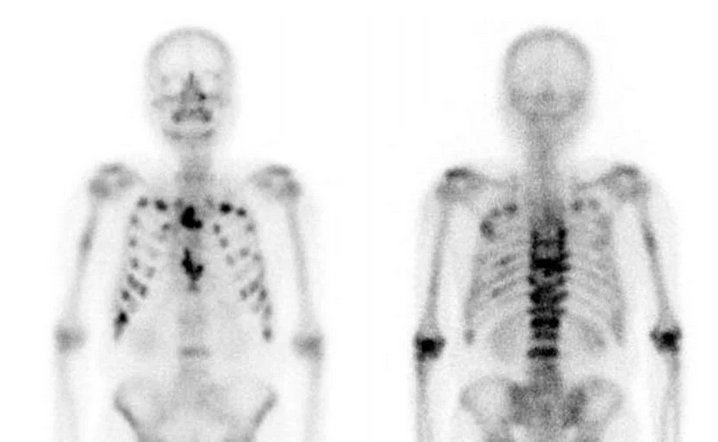

Σπινθηρογράφημα οστών – Παρουσία πολλαπλών οστεολυτικών εστιών (Ευγενική παραχώρηση Dr. V. Penopoulos)